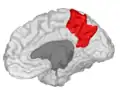

Precuneus of left cerebral hemisphere (shown in red). -